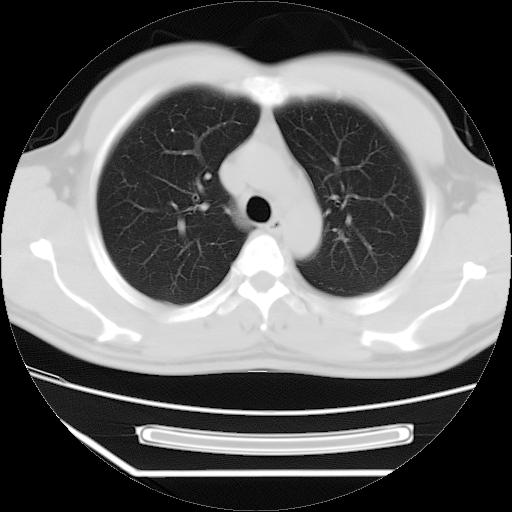

男,38岁,于2009年8月9日晚突发左侧胸痛,今x线提示左下肺阴影,为了明显确诊断,行ct检查,

血常规:嗜酸性细胞增高,单核细胞增高。

病灶发生在下叶,密度均匀,边缘模糊、毛糙,周围血管纹理增强扭曲改变,靠近胸膜处病灶胸膜反应明显。

支持考虑---球形肺炎。

左肺舌叶病变。主体病灶呈类圆形中心密度低,成液化趋势周边班片影分布

考虑肺脓肿

虽然实验室检查支持炎性病变,且病变内有坏死改变(中央呈大片状低密度影),但仍不能掉以轻心,鳞癌也可以有这种影像改变。